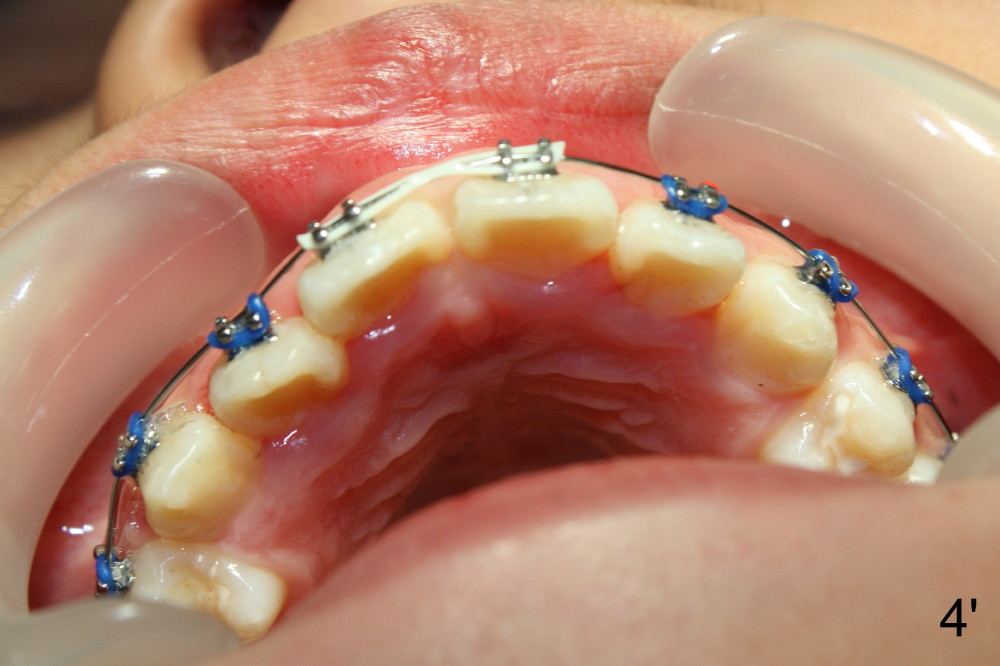

| Fig.4: Immediately post banding and bracketing, .012 niti | Fig.4': One month post banding and bracketing, .014 niti |

The upper arch is more rounded one month of orthodontic treatment (Fig.4'). UR1 rotation (Fig.4) is corrected (Fig.4'). The rotation wedge was removed; power chain was placed between U1s to close the diastema and make room for UR2 to move labially.

If there is a diastema between UL1 and 2 and there is not enough room for UR2 next appointment, consider using power chains between UR1 and UL3 (The statement is proposed on 10/06/2013. Why to involve UL3?). Did we do it today (11/09/2013, Fig.4'')? There is a space between UL1 and 2 (<). The arch wire is not fully engaged in the mesial bracket of the UR2 (^). Nobody reviewed the case before the last appointment. We should not miss it again next visit.